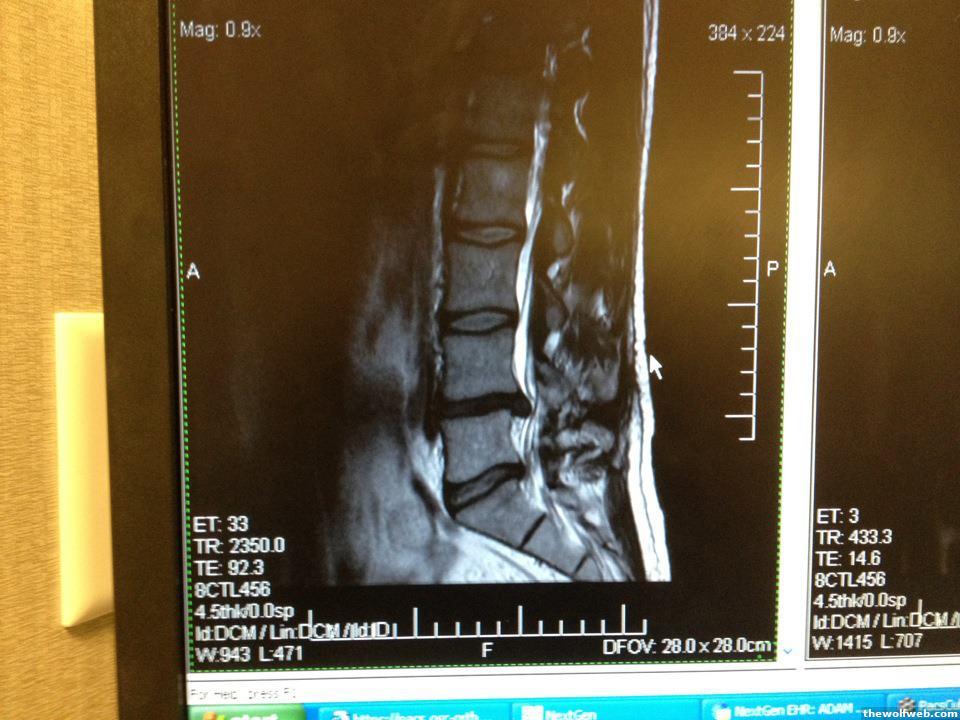

I knooooowwww. How the fuck did you end up with a fusion considering your MRI looks more tame than mine. WTF.

In the first month and half( and we are talking back in late November), I did have minor numbness on the outerside of my left foot, and I still have residual numbness on my outer left thigh, but not my toes anymore. That was what's concerning to the first Orthopedic surgeon.

That's also what's prompted me to get different opinions from neurosurgeons as well. The more I think about, the more I think this is the best way to go if I ever want to get back to normal actvities.

My injury is right in the spinal canal that the endoscope would have easy access to the disc material. At least that is my guess and that is what it looks like in the MRI.